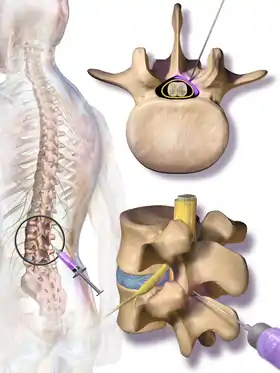

Treatment options for NC aim to cure the underlying cause of the condition, such as lumbar spinal stenosis (LSS) or other degenerative spinal diseases. Decreased walking and lower body motor ability due to NC is the primary disabling feature of LSS.[17] Constant discomfort and pain in the lower extremities and an inability to sleep lying down are also disabling features of NC that affect a patient's quality of life. Therefore, the target of most treatments is to solve these complications.[17] Currently, several treatment options are available to patients, and they can be grouped broadly into nonsurgical and surgical options.[17][7] Nonsurgical treatments include medications, physical therapy, and spinal injections. Medication options for neurogenic claudication have included non-steroidal anti-inflammatory drugs (NSAIDs), prostaglandin-based drugs, gabapentin, and methylcobalamin. However, the quality of evidence supporting their use is not high enough for specific recommendations. Physical therapy is commonly prescribed to patients, but the quality of evidence supporting its use for neurogenic claudication is also low.[10] One quarter of all epidural injections are administered to treat symptoms of LSS.[17] Preparations may contain lidocaine and/or steroids. They may be considered for short-term pain relief or to delay surgery, but their benefit is considered small.[1]

Medications such as NSAIDs, prostaglandin-based drugs, gabapentin, methylcobalamin and epidural steroid injections are often used in conjunction with physical therapy to treat patients with mild or moderate symptoms of NC.[15] The main goal of these medications is to reduce pain and provide temporary relief for NC patients. NSAIDs and prostaglandin-based medications control inflammation at sites of nerve damage or pressure by inhibiting cyclooxygenase activity, and reducing the production of prostaglandins, a key contributor of inflammation.[24][25] By reducing inflammation, less pressure is put on the nerve roots, decreasing pain, and providing relief for NC patients.[26] Gabapentin aims to reduce pain and provide relief by altering the normal functioning of neurotransmitters that induce a sensation of pain and discomfort.[27] However, the exact mechanism of Gabapentin’s functioning in the body is not completely understood and current knowledge is based on experimental studies that target the nervous system.[28] Methylcobalamin is another medication that targets the nervous system to reduce pain and provide NC patients with temporary pain-relief. The drug produces myelin to cover and protect nerves from damage, preventing pain induced from damaged nerve roots, as described in some cases of NC.[29] Epidural steroid injections are the main epidural injections prescribed to treat NC. They inhibit the inflammatory cascade signalling to reduce inflammation at sites of spinal nerve damage or pressure. Consequently, they reduce pain and provide relief to individuals with NC.[30][31] Whilst the use of medications is common among NC patients that experience frequent or constant pain, their effectiveness has yielded mixed results in studies.[27][32] Further research into their viability as a medication for NC is necessary to allow doctors to provide better care and treatment options for NC patients.[33]

Depending on the cause and severity of the condition, surgical options for NC vary. Symptoms of LSS, including NC, are the most common reason patients 65 and older undergo spinal surgery. Surgery is generally reserved for patients whose symptoms do not improve with nonsurgical treatments, and the main objective of surgery is to relieve pressure on the spinal nerve roots and recover normal mobility and quality of life.[10] Lower Spinal Decompression is considered the mainstay of surgical treatment.[2] In this procedure, the ligamentum flavum is first removed, followed by the removal of the superior facet osteophyte in the spinal canal, and then the decompression of the spinal nerve root.[5][11] Another surgical method of decompression is the Fenestration method, which involves creating a small window in the spinal canal and then decompressing the nerves.[8] Alternative surgical options include the use of interspinous process spacers, minimally invasive lumbar decompression (MILD) procedure, laminectomy, microdiscectomy and placement of a spinal cord stimulator. The MILD procedure aims to relieve spinal cord compression by percutaneous removal of portions of the ligamentum flavum and lamina.[10] Laminectomy also involves partial or complete removal and sacrifice of the lamina, but in addition, facets in one or more segments of the spinal cord are usually sacrificed as well.[8][11] Microdiscectomy is another surgical alternative which uses small incisions, and a miniature camera for viewing, to enter the spinal cord and release pressure on the nerve roots.[5][8] Laminoplasty and spinal fusion surgeries are other alternative surgical procedures that can be performed. However, they are relatively new methods which still require more research and advancements in order for it to be safely performed with minimal risks.[11][34]